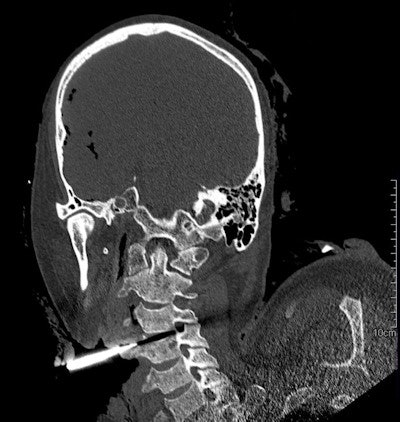

Multiple specialties are involved in the lifesaving work needed for knife-crime victims. The importance of swift radiologic examination in the emergency room is crucial to the success of surgery in an unpredictable trauma situation.

Because many stabbing victims die before reaching hospital it is vital the trauma team has as much information about the site of the wound(s) and can arrange to have the radiology team on standby or the use of a mobile machine depending on wound location, weapon, and ease of accessibility. Positioning patients may present a challenge as often the weapon remains in situ until it can be removed in a controlled surgical situation.

The radiological evaluation of penetrating knife injuries can be daunting given the emergency circumstances requiring imaging. The challenges facing the radiologist in imaging assessment of penetrating trauma impacts significantly on the effective management of these patients in the acute setting.

CT's increasing value

The management of these injuries has changed over the years, Dr. Jon Gonzalez Ocio, a radiologist at Cruces University Hospital in Barakaldo, Spain, told attendees at ECR 2019. At the beginning of the 20th century, the treatment was surgical in all cases, but in the mid-1960s, authors advocated conservative treatment, given the high incidence of negative laparotomies and the risks they entail for the patient. Imaging techniques became increasingly important.

In particular, the development of software that allows multiplanar reconstructions has boosted the value of CT.

"We must remember that CT is indicated in those cases in which the patient is already stabilized. If the patient is not stable, the guidelines indicate the correct action that decreases the mortality is the surgical intervention," he said.